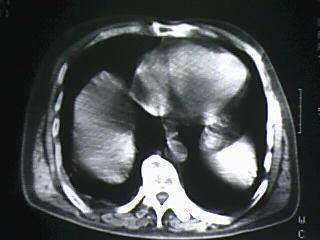

标题: CT19768:男 61岁 胸痛 咯血 一周。无发烧、无结核病史。 [打印本页]

标题: CT19768:男 61岁 胸痛 咯血 一周。无发烧、无结核病史。

纵隔窗图像不佳,怀疑右下叶支气管有狭窄,来几张清楚的,暂考虑----感染性病变----抗炎后复查

考虑 右下肺感染性病变,建议抗炎后复查。

考虑右肺下叶感染性病变;建议抗炎治疗后复查。